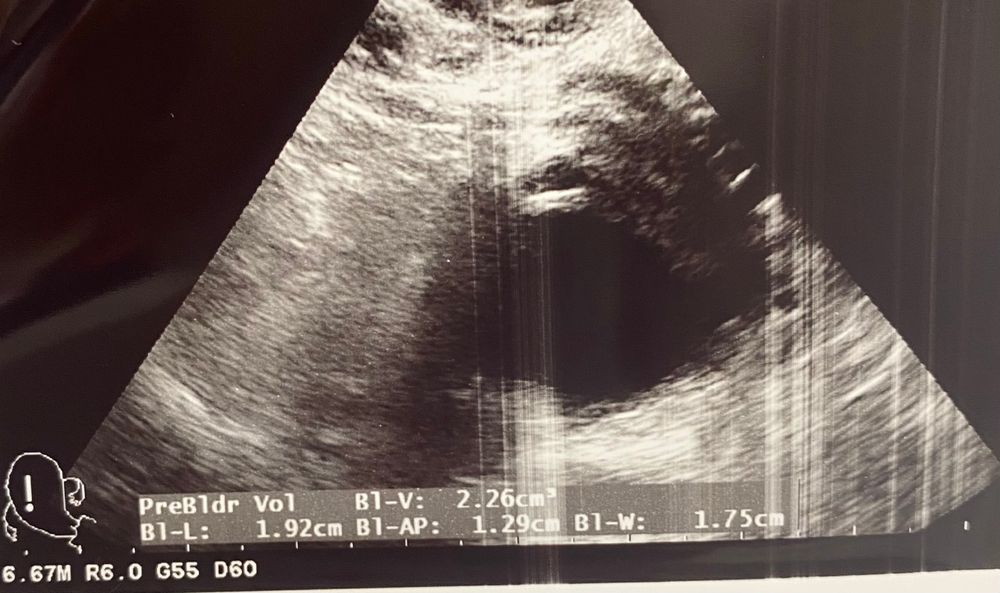

Виктория, такой был до укола хгч три дня назад, в вопросе вчера Изображение

Виктория, предполагаю, что фолликул, с прошлого цикла не могла остаться, так как пила 3 мес КОК и ходила на 11 дц на узи были маленькие фолликулы, кист не было, сейчас 27 ДЦ, фолликул был 20 только на 24 дц, потом был укол ХГч

Виктория, а эхогенное образование бывает в желтом теле? узист была не моя, моя в отпуске. За день до этого моя говорила, что фолликул 20 мм и эндометрий 10. А вот эта сказала, что после укола не лопнул и вообще он 18 мм. А эндометрий 6! Куда делся за полутора суток. Могу предположить, что сдулся. Моя мерила через день и в субботу он уже был 18! Поэтому ничего не понятно. Да и фолликул последний на фолликул не похож